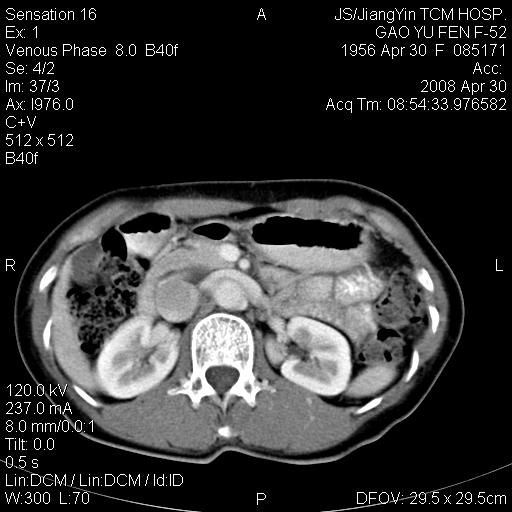

标题: CT13307:肠系膜囊肿? [打印本页]

标题: CT13307:肠系膜囊肿?

囊性淋巴管瘤可能比较大。

良性囊性占位,来源于肠系膜的可能性大

图像少,不能连续起来看,不太敢确定囊肿前方的条状结构是十二指肠水平段?如果是,那肠系膜囊肿,淋巴管瘤都有可能。

病变位于肾静脉后方,支持腹膜后占位性病变,以囊性淋巴管瘤可能性大.